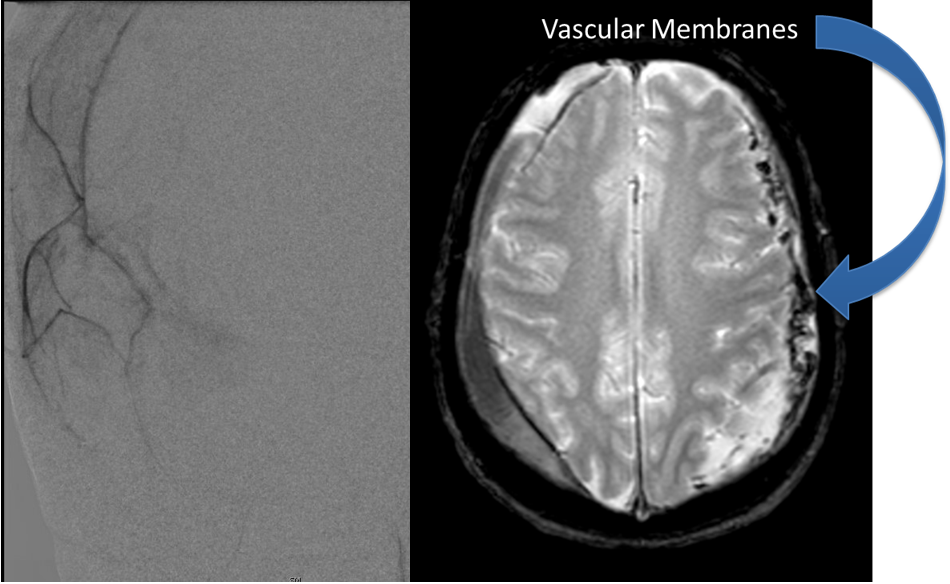

Brain:

Neurosurgeons Collaborate to Treat Giant Symptomatic Meningioma

Author: Ramin Rak M.D., F.A.A.N.S., F.C.N.S., Jonathan L. Brisman M.D., F.A.C.S., Read More!

Atypical Convexity Meningioma

Author: Jonathan L. Brisman M.D., F.A.C.S., Read More!